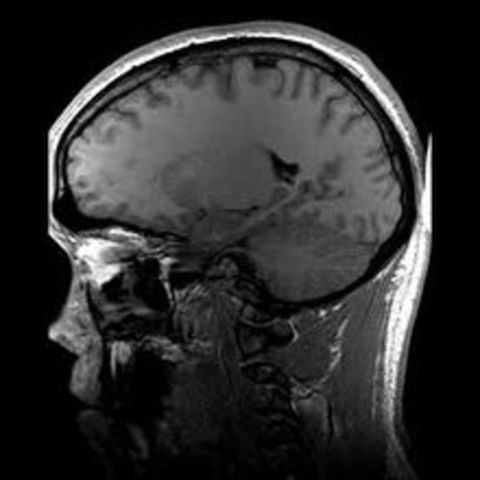

• M.R.I

M.R.I

Dr. Raymond V. Damadian announced that he had patented a technique using nuclear magnetic resonance to distinguish between normal and cancerous tissue. In 2003, two other researchers won a Nobel Prize for further discoveries.